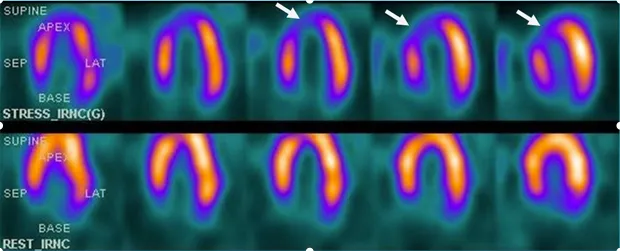

SPECT myocardial perfusion imaging (MPI) employs technetium-99m-based radiotracers-sestamibi or tetrofosmine-that distribute proportionally to coronary blood flow. The two-day stress-rest protocol administers 25-30 mCi at peak stress and 25-30 mCi at rest, with imaging performed 30-60 minutes post-injection to allow hepatic clearance.

📌 Remember: RIPS for SPECT defect patterns-Reversible means ischemia, Irreversible suggests scar, Partial reversal shows mixed pathology, Severe when involving >10% myocardium requiring intervention.

Specific scintigraphic patterns identify patients requiring aggressive management regardless of symptom severity. These high-risk markers predict annual cardiac event rates exceeding 5%, warranting coronary angiography and consideration for revascularization.

⭐ Clinical Pearl: Transient ischemic dilation demonstrates 85% specificity for severe three-vessel or left main disease, elevating annual cardiac event risk to 8-12% even when ischemic burden appears moderate (5-10% of myocardium), mandating invasive evaluation regardless of stress test functional capacity.